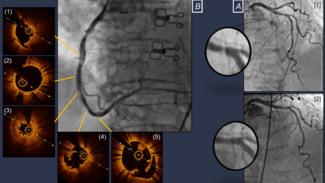

Charles Gallen, MD; Amine Boussofara, MD; Quentin Landolff, MD

A 67-year-old man who was overweight, hypertensive, and had no cardiovascular medical history was treated for a lateral myocardial infarction due to a ramus coronary branch occlusion.